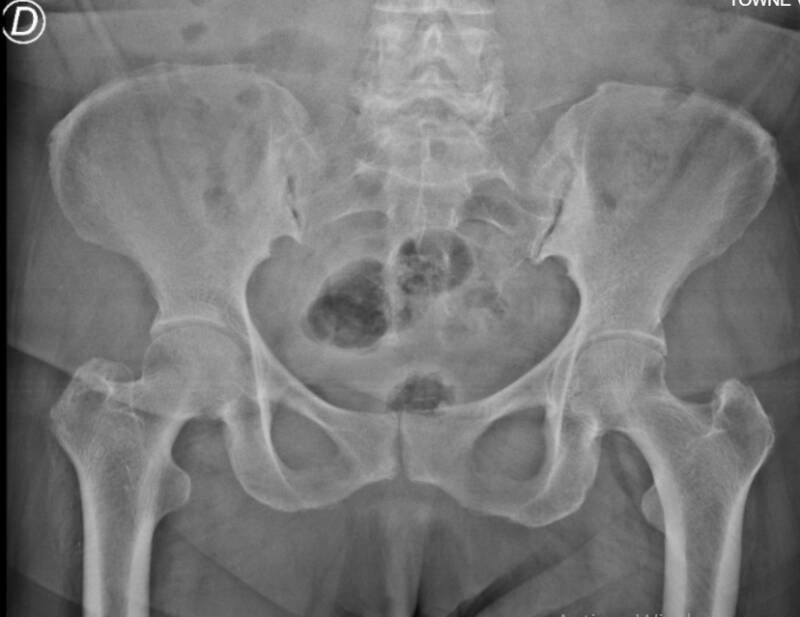

V. Sistema Musculoesquelético

16. Región Femoral (Muslo)

Segmento de la extremidad inferior que comprende el fémur y potentes grupos miotendinosos.

Resonancia Magnética (10/10): Excelencia en la valoración de desgarros musculares y sarcomas de partes blandas.

Radiología Simple (8/10): Evaluación primaria de la integridad cortical ósea y fracturas.

Ecografía (7/10): Evaluación dinámica de lesiones musculares superficiales.

17. Articulaciones (Cadera, Rodilla, Mano)

Estructuras de unión ósea diseñadas para la movilidad.

Resonancia Magnética (10/10): Gold standard para ligamentos, meniscos, fibrocartílagos y edema óseo.

Radiología Simple (9/10): Primer escalón para el diagnóstico de artrosis y enfermedades inflamatorias articular. Es una de las areas donde la radiología permanece con un estudipo de imagenes de gran valor a pasar de los años.

Gammagrafía Ósea (8/10): Evaluación de la actividad metabólica en patología metastásica poliostótica.

Tomografía Computarizada (6/10): Reconstrucción tridimensional útil en la planificación quirúrgica de fracturas articulares complejas.